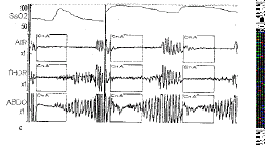

c

图3 各 种典型的Ⅲ型曲线

(3)Ⅲ型曲线(type Ⅲ):发生于部分呼吸紊乱的后期,期间鼻口气 流减少50%,胸式和腹式呼 吸动度均出现≥50%的呼吸运动,其前期均由Ⅰ型曲线构成。

1.3.2 患者分类 轻度阻 塞性睡眠呼吸暂停综合征:呼吸紊乱曲线以Ⅰ型曲线为主,少量Ⅱ型、Ⅲ型曲线未超过Ⅰ型 曲线的50%。中度阻塞性睡眠呼吸暂停综合征:超过50%的Ⅰ型曲线后出现Ⅱ型、Ⅲ型曲线, 且以Ⅱ型曲线为主。重度阻塞性睡眠呼吸暂停综合征,超过50%的Ⅰ型曲线后出现Ⅱ型、Ⅲ 型曲线,以Ⅲ型曲线为主。